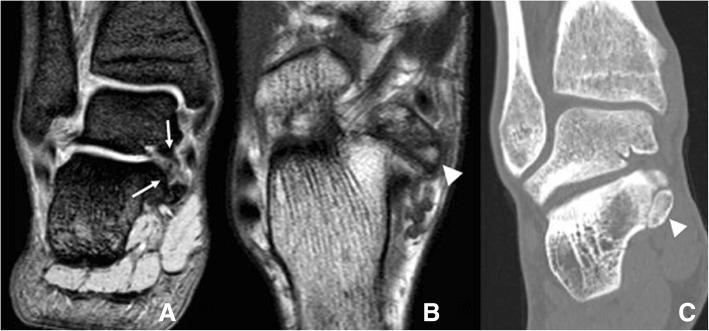

Accessory anatomical structures in the ankle and foot usually represent incidental imaging findings; however, they may also eventually represent a source of pathology, such as painful syndromes, degenerative changes, be the subject of overuse and trauma or appear as masses and cause compression syndromes or impingement.This review aims to describe and illustrate the imaging findings related to the presence of accessory ossicles and muscles in the ankle and hindfoot through different techniques, with special attention to those variants that associate factors of clinical relevance or that trigger challenges in the differential diagnosis.

踝关节和足部的附属解剖结构通常为偶然的影像学表现;然而,它们最终也可能成为病理来源,如疼痛综合征、退行性改变、过度使用和创伤的对象,或表现为肿块并导致压迫综合征或撞击。本综述旨在通过不同技术描述和展示与踝关节和后足附属小骨和肌肉存在相关的影像学表现,特别关注那些与临床相关因素相关或在鉴别诊断中引发挑战的变异。